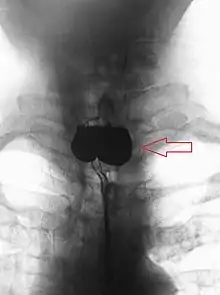

A Zenker's diverticulum, also pharyngeal pouch, is a diverticulum of the mucosa of the human pharynx, just above the cricopharyngeal muscle (i.e. above the upper sphincter of the esophagus). It is a pseudo diverticulum (not involving all layers of the esophageal wall).

More precisely, while traction and pulsion mechanisms have long been deemed the main factors promoting development of a Zenker's diverticulum, current consensus considers occlusive mechanisms to be most important: uncoordinated swallowing, impaired relaxation and spasm of the cricopharyngeus muscle lead to an increase in pressure within the distal pharynx, so that its wall herniates through the point of least resistance (known as Killian's triangle, located superior to the cricopharyngeus muscle and inferior to the thyropharyngeus muscle. Thyropharyngeus and cricopharyngeus are the superior and inferior parts of inferior constrictor muscle of pharynx respectively). The result is an outpouching of the posterior pharyngeal wall, just above the esophagus.[3]

A combination of the simple barium swallow and a thorough endoscopy will normally confirm the diverticulum.[4]